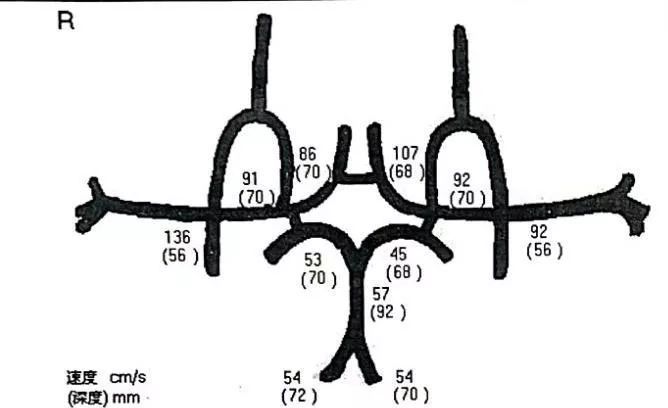

↑↑↑TCCD提示:同侧颈内动脉颅内段、大脑中动脉无狭窄。

图6:复查造影时行TCD检查

图9:术后第二天复查TCCD